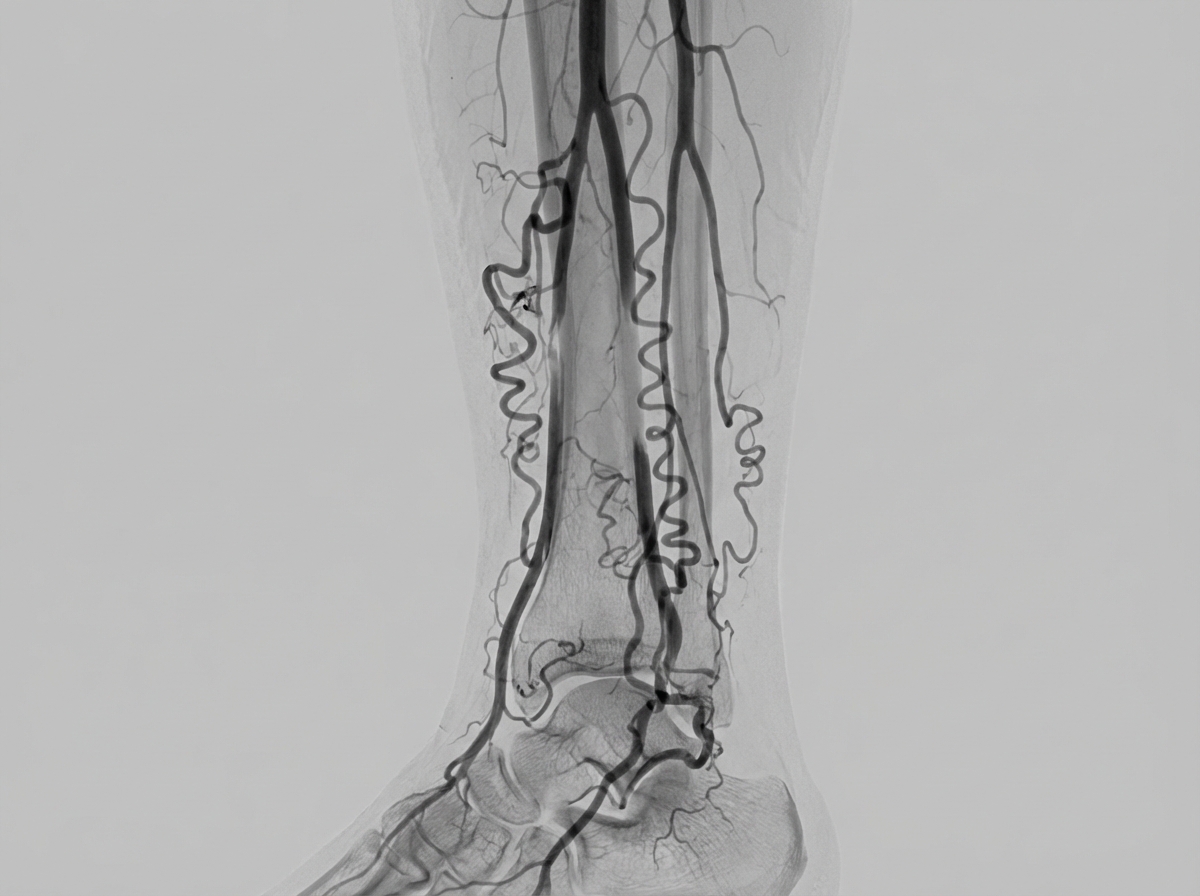

The angiogram depicted below is most typical of a patient whose history includes:

Explanation: ***Cigarette smoking*** - The angiogram shows characteristic **corkscrew collateral vessels** and **segmental occlusions** typical of **Buerger's disease (Thromboangiitis Obliterans)**, which is strongly associated with cigarette smoking. - **Skip lesions** with normal intervening segments and prominent collateral circulation are pathognomonic findings in young smokers with peripheral vascular disease. *Alcoholism* - Alcoholism primarily causes **cardiomyopathy** and **hepatic cirrhosis** rather than the specific vascular changes seen in this angiogram. - Does not typically produce the characteristic **segmental arterial occlusions** and **corkscrew collaterals** shown in the image. *Hypertension* - Hypertensive vascular disease typically shows **diffuse arterial narrowing** and **smooth tapering** rather than segmental occlusions. - The angiographic pattern would demonstrate **generalized atherosclerotic changes** without the distinctive collateral vessel formation seen here. *Diabetes* - Diabetic vascular disease commonly affects **small vessels (microangiopathy)** and shows **diffuse atherosclerotic narrowing**. - The pattern typically involves **calcified vessels** and **diffuse stenosis** rather than the segmental occlusions and prominent collaterals characteristic of Buerger's disease.